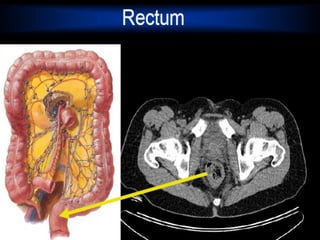

Regions of Large Intestine

Rectum –terminal end is anal canal - ending at the anus - which has internal

involuntary sphincter and external voluntary sphincter

Cecum – pocketat proximal end with Appendix Colon Ascending colon - on right, between cecum and right colic flexure Transverse colon - horizontal portion Descending colon - left side, between left colic flexure and Sigmoid colon - S bend near the terminal end Regions of Large Intestine Rectum –terminal end is anal canal - ending at the anus - which has internal involuntary sphincter and external voluntary sphincter